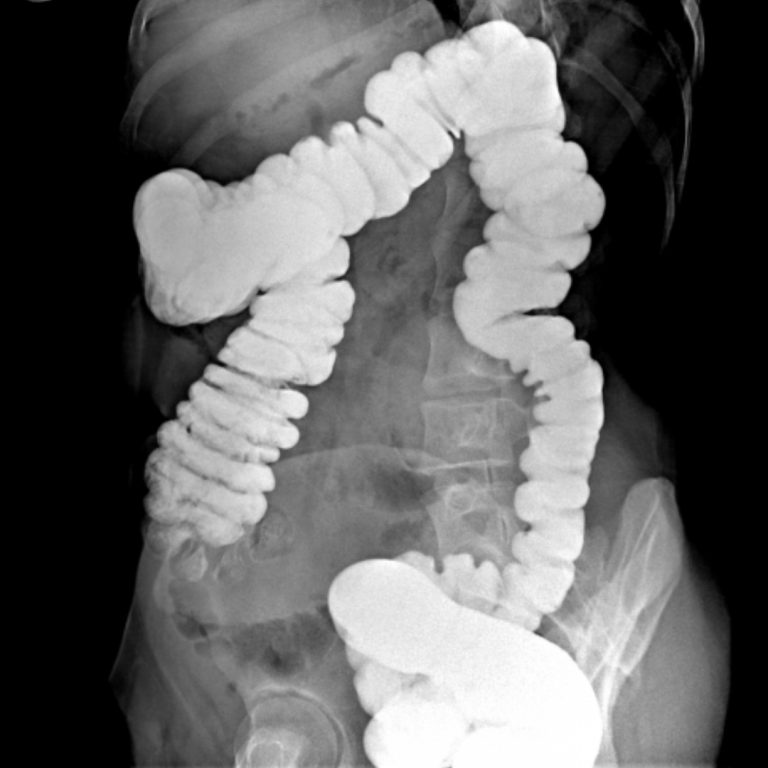

İki çeşit baryumlu kolon incelemesi vardır; tek kontrast ve çift kontrast. Kolon kanseri taramasında genellikle çift kontrastlı kolon tetkiki kullanılır.

2- Çift Kontrastlı Kolon grafisi

Bu işlemin tek kontrastlı tetkikten en önemli farkı, kolonun hava ile doldurulmasıdır. Böylece daha kaliteli görüntü elde edilir. Polip gibi daha küçük lezyonlar rahatlıkla seçilebilir. Kolon tetkiki 20-30 dakikada tamamlanmakla birlikte, nadir durumlarda 45 dakikaya kadar çıkabilir. Bu tetkik karında hafif kramplara neden olabilir. Tetkikin bitimi ile şikâyetler sonlanır. Tetkik bitince rektuma yerleştirilen tüp çıkarılır ve kolonun boşaltılması istenir. Tetkiki takip eden birkaç gün dışkı, içeride kalan baryuma bağlı olarak beyaz, gri veya pembe görünümde olabilir. Geride kalan baryum kabızlığa neden olabileceğinden bol miktarda su içilmesi tavsiye olunur.

Rektal yoldan verilen kontrast madde takıntısız çekuma ulaşmış olup ilioçekal bileşke serbesttir. Apendiks vizüalize olmuştur ve normal görünümdedir. Rektum posterior konturu muntazamdır. Presakral mesafe açıktır. Kolon boyunca belirgin haustrasyon artışı mevcuttur. Sigmoid kolon hafif elonge görünümdedir. Kolon lümeninde doluş defekti lehine bulgu saptanmamıştır. Evakuasyon fazında sağ kolon ve hafif sigmoid kolon içinde remnant kontrast madde kalmıştır. Diğer segmentlerdeki kontrast maddenin bulunmaması mukozanın ödemli olabileceğini düşündürmektedir. Çift kontrastlı grafiler ve sağ kolondaki kontrast maddesinin fragmane olduğu dikkati çekmektedir. Bulgular irritable kolonla uyumlu bulunmuştur.